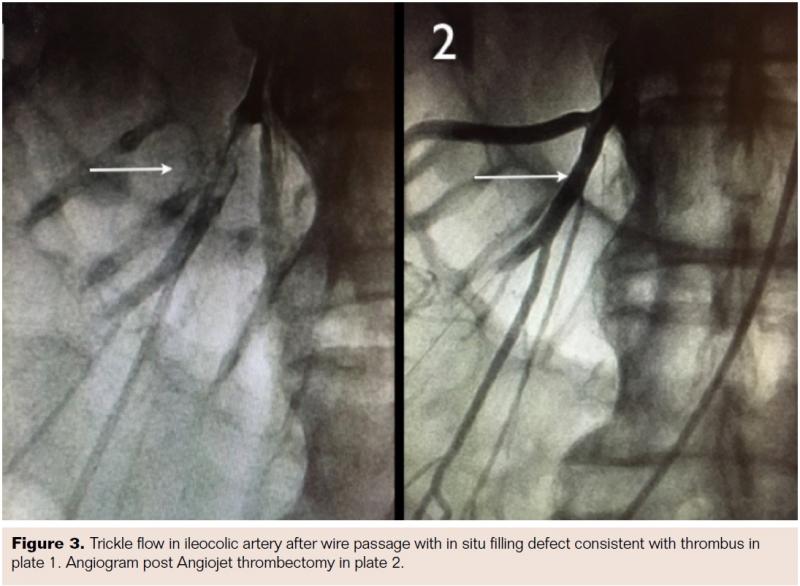

The patient was taken for urgent angiography due to rapid rise in biomarkers reflecting early bowel necrosis. Right femoral artery access was obtained and cannulated with a 6 Fr sheath. A 4 Fr internal mammary catheter was used to cannulate the superior mesenteric artery (SMA). The catheter was advanced into the proximal segment of the vessel over a Glidewire (Terumo). Angiography via the internal mammary catheter confirmed the CT angiographic findings. This catheter was exchanged for a 6 Fr, 55 cm Ansel guiding sheath (Cook Medical). Activated clotting time was 177 seconds, and heparin 3,000 U bolus was administered intravenously. A 0.014˝ wire was advanced through the occluded distal SMA and thrombectomy was done using an Angiojet XVG thrombectomy catheter with complete resolution of the thrombus (Figure 2). The wire was then advanced into the ileocolic artery, which was treated with a similar technique (Figure 3). The proximal segment of the ileocolic artery showed thrombus resolution but a large branch of this vessel was still occluded. Thrombectomy in this branch did not re-establish flow in the vessel, and the angiographic appearance was consistent with diffuse spasm. A 135 cm Cragg-Mcnamara Valved Infusion Catheter (Medtronic) with 10 cm infusion length was then advanced into this branch (Figure 4) and intra-arterial papaverine was administered via this catheter at 30 mg/hr. An intravenous heparin drip was administered peripherally at 500 U/hr.